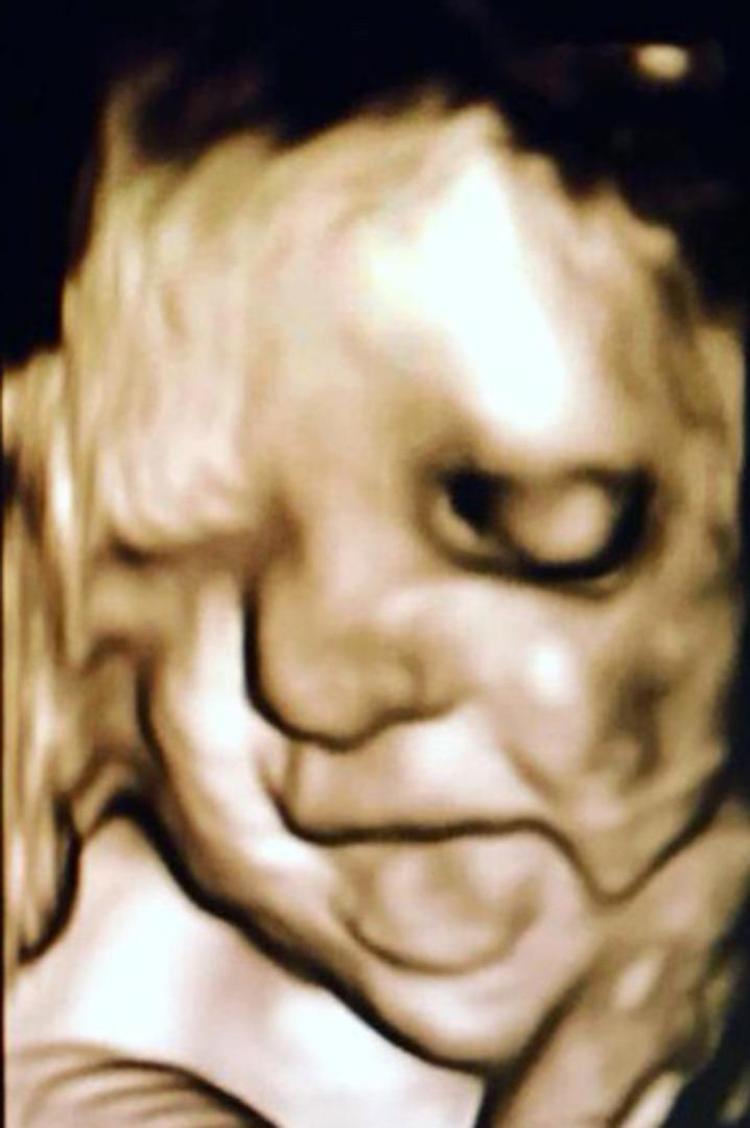

HaberlerFoto Galeri Haberleri Anne karnındaki bebeklerin gülümseten pozları Anne karnındaki bebeklerin gülümseten pozları. • Son Güncelleme: 20 Şubat 2020 - 09:11 • Son Güncelleme: 20 Şubat 2020 - 09:111 23456789101112